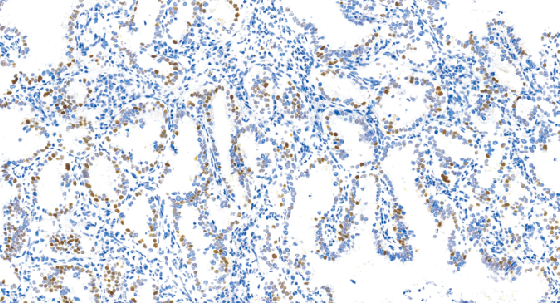

Cyclin E1兔抗人细胞周期蛋白E1单克隆抗体

人类细胞周期蛋白E蛋白基因编码几种多脑,分子量范围为39至52kDa。Cyclin E1在细胞周期的G1晚期至S期的结束时表达。CyclinE1在恶性肿瘤中的表达比正常细胞要高,此蛋白的表达与不同癌症的进展有关,如乳腺癌、白血病、淋巴瘤和其他类型的肿瘤。

- 阳性部位:胞核

- 适用组织:石蜡切片

- 预处理:热修复